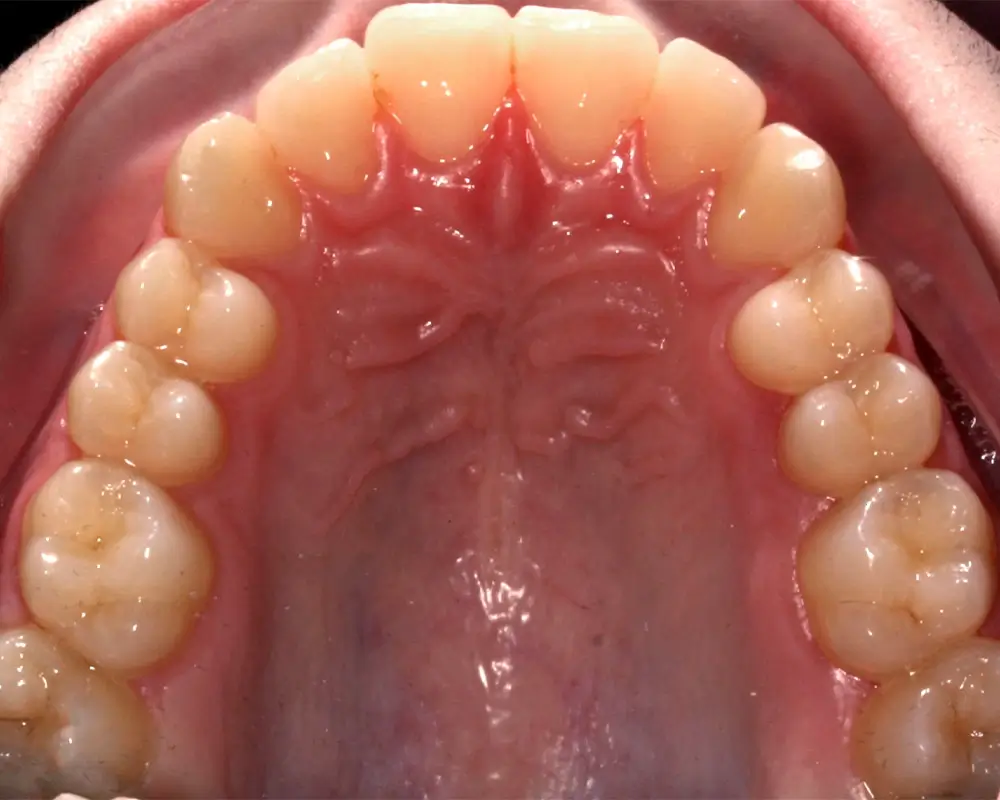

Скученность - Кейс 25

Эффективность устранения дефекта прикуса посредством элайнеров FlexiLigner.

16

Количество кап НЧ

Результаты лечения